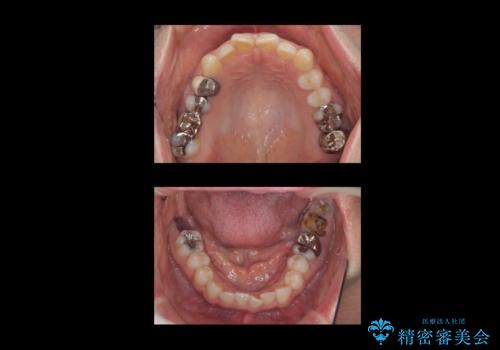

下の奥歯が虫歯になっており、痛みが生じていました。

左右の第二大臼歯は虫歯がひどく抜歯が必要な状態でした。

また、左下の第一大臼歯は歯が内側から吸収してしまう状態(外部吸収)が生じており、患者様と相談の上抜歯しました。

合計3本の奥歯を抜歯したところに、インプラント治療を行っています。